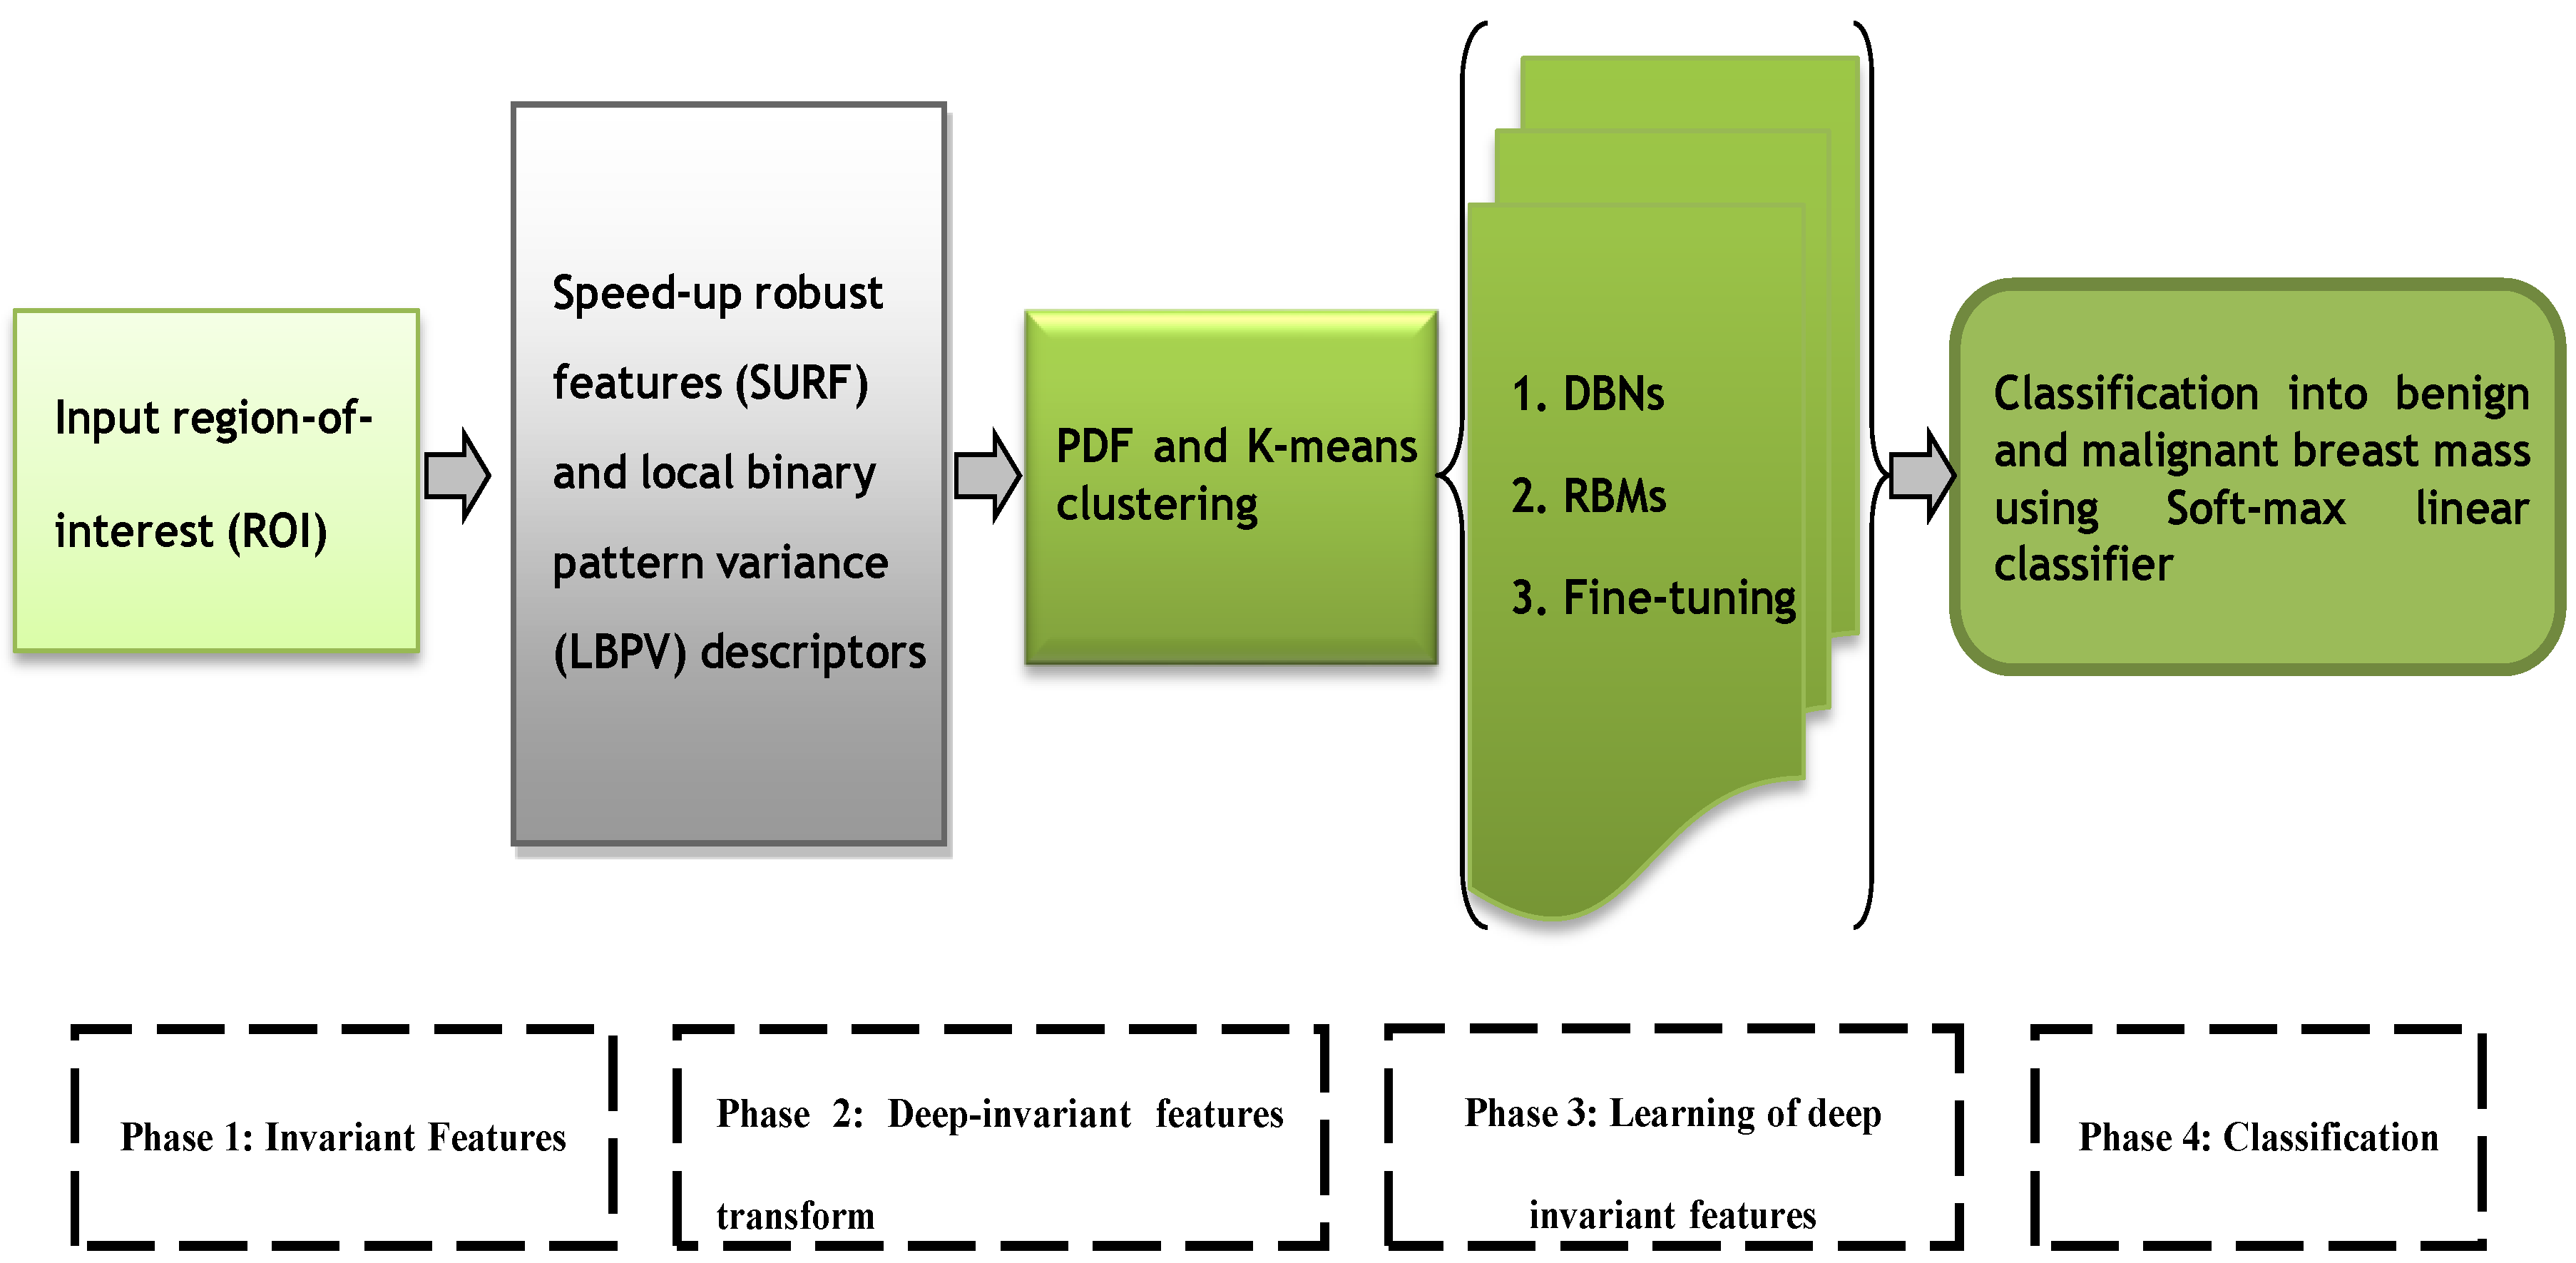

The speed-up robust features (SURF) [

Figure 1.

The major steps of the proposed DeepCAD system consist of extraction of invariant features, transform to deep invariant features (DIFs), multilayer deep-learning and softmax layer for classification. All these phases are graphically represented by

Figure 1. All these phases are briefly explained in the subsequent sections.